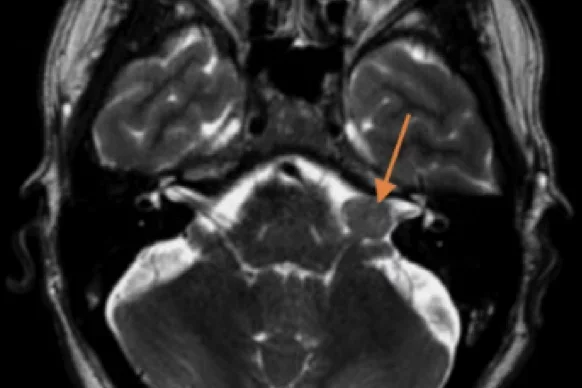

Diagnosis of VS often follows a patient presenting with otological or neurological symptoms. Pure tone audiometry, digital subtraction angiography, otoscopy, CT scanning, and MRI imaging can be used to investigate the presence of a schwannoma.

MVI Measured on axial T2-weighted MR images using the ITK-SNAP software.